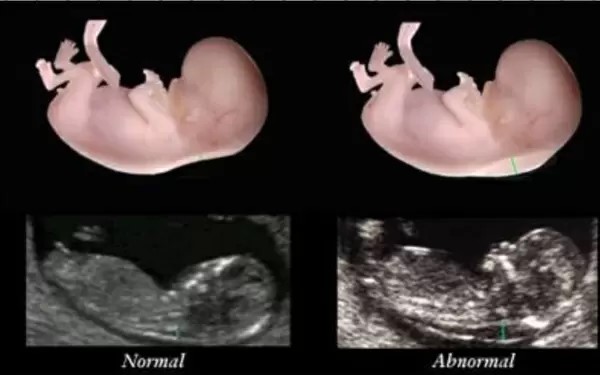

Xét nghiệm độ mờ da gáy (nuchal translucency) là một xét nghiệm được thực hiện trong thời kỳ mang thai.

Bác sĩ sẽ sử dụng sóng siêu âm để đo độ dày của chất lỏng tích tụ ở phía sau cổ của em bé đang phát triển. Đây là một cách để kiểm tra nguy cơ mắc một số dị tật bẩm sinh của thai nhi. Chẳng hạn như hội chứng Down, hội chứng Edward (tam nhiễm sắc thể 18), tam nhiễm sắc thể 13 và nhiều bất thường nhiễm sắc thể khác, cũng như các vấn đề về tim.

Tỷ lệ chính xác của siêu âm độ mờ da gáy trong việc xác định các yếu tố nguy cơ bất thường nhiễm sắc thể ở trẻ sơ sinh là 70 đến 75%. Vì vậy, kết quả của xét nghiệm này chỉ được dùng để sàng lọc chứ không được làm chỉ số chẩn đoán.

Xét nghiệm độ mờ da gáy bằng siêu âm 4D

Hiện nay, siêu âm 4D được xem là siêu âm thai hiện đại nhất, có thể giúp thai phụ nhìn rõ được cấu trúc xương mặt của tai nhi. Tuy nhiên, trong siêu âm độ mờ da gáy, siêu âm 4D sẽ cho kết quả không chính xác. Vì vậy, siêu âm đo độ mờ da gáy được thực hiện bằng sóng siêu âm 2D sẽ cho kết quả chính xác hơn.

Chỉ số xét nghiệm độ mờ da gáy bình thường và bất thường

Độ mờ da gáy ở cổ thai nhi theo thời gian sẽ càng ngày càng giảm. Nếu chỉ số xét nghiệm độ mờ da gáy có dấu hiệu tăng lên bất thường trong mỗi lần kiểm tra thì thai phụ không nên chủ quan. Tham chiếu chỉ số đo độ mờ da gáy với chỉ số tiêu chuẩn sau đây để biết có bất thường gì không.

– Nếu tuổi của thai nhi tại thời điểm siêu âm độ mờ da gáy chưa được 12 tuần thì chỉ số đo độ mờ da gáy không được vượt quá 2.5mm.

– Nếu thai từ 12 – 13 tuần khi đo độ mờ da gáy thì chỉ số đo độ mờ da gáy không được vượt quá 3mm.

– Nếu chỉ số độ mờ da gáy khi thai được 11 – 14 tuần cao hơn 3mm thì cần làm thêm những xét nghiệm khác để đánh giá bất thường trong nhiễm sắc thể. Ở lần xét nghiệm đầu tiên, chỉ số vượt quá mức bình thường thì nên lưu ý bởi đây là dấu hiệu nguy cơ bất thường nhiễm sắc thể giới tính hoặc bệnh tim bẩm sinh là tương đối cao.